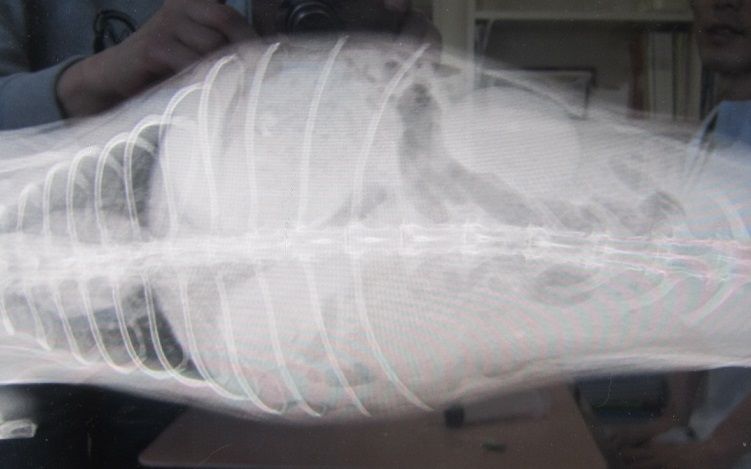

レントゲン

胸、心臓付近、胃はとくに問題なく、触診通り、

盲腸にすごいガスが発生してて、“盲腸うっ滞” とな。

“盲腸便秘”

すごく焦った。まだまだ元気はあるし、これでも猶予があるのだけれど、

やっぱこのコントラストは焦る。